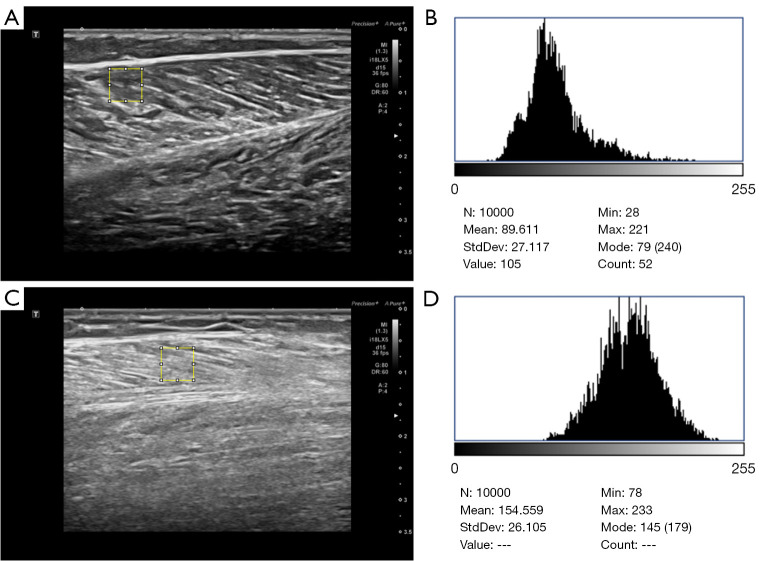

Background: Sarcopenia, an age-related condition marked by progressive muscle loss and dysfunction, is a growing clinical and public health challenge. While current diagnostic methods involve limitations in cost, accessibility, and assessment of muscle quality, ultrasound offers a practical alternative. This study examined grayscale histogram analysis of gastrocnemius muscle ultrasound images as a novel quantitative method for diagnosing sarcopenia by evaluating its ability to detect textural changes associated with intramuscular fat infiltration and fibrosis, with the ultimate aim of establishing an accurate, accessible diagnostic approach.

Methods: A retrospective case-control study was conducted on 101 patients diagnosed with sarcopenia who were admitted to the Department of Endocrinology at Shandong Provincial Hospital between March and December 2024. Additionally, 101 healthy volunteers who underwent health examinations in our hospital during the same period were recruited as the control group. Grayscale histogram parameters, including the minimum gray value, maximum gray value, median gray value, mean gray value, standard deviation of gray values, skewness, kurtosis, and the gray values corresponding to seven percentile points (quantile 5, quantile 10, quantile 25, quantile 50, quantile 75, quantile 90, quantile 95) were extracted from the ultrasound images of the participants' gastrocnemius muscles. Statistical methods were used to analyze the differences between the sarcopenia and control groups. Receiver operating characteristic (ROC) curves were used to compare the differential diagnostic efficacy of each parameter and their combinations. Linear regression and least absolute shrinkage and selection operator (LASSO) were used to predict the probability of sarcopenia, with model performance evaluated with R2 values and the mean square error.

Results: The grayscale histogram parameters of the gastrocnemius ultrasound images in the sarcopenia group, including the minimum gray value, maximum gray value, median gray value, mean gray value, standard deviation of gray values, and the gray values corresponding to seven percentile points, were significantly higher than those in the control group (P<0.001), while both the skewness and kurtosis were smaller than those in the control group (P<0.001). The gray value corresponding to quantile 75 demonstrated the best diagnostic efficacy [area under the curve (AUC) =0.988, sensitivity =96%, specificity =95%] at a cutoff of 132.5. The LASSO regression model outperformed linear regression (test set: R2 =0.769 vs. 0.727; mean square error =0.057 vs. 0.068).

Conclusions: The grayscale histogram parameters extracted from ultrasound images may be able to quantitatively reflect the differences between patients with sarcopenia and healthy individuals to some extent. Grayscale histogram analysis based on ultrasound images could be valuable for the diagnosis of sarcopenia.